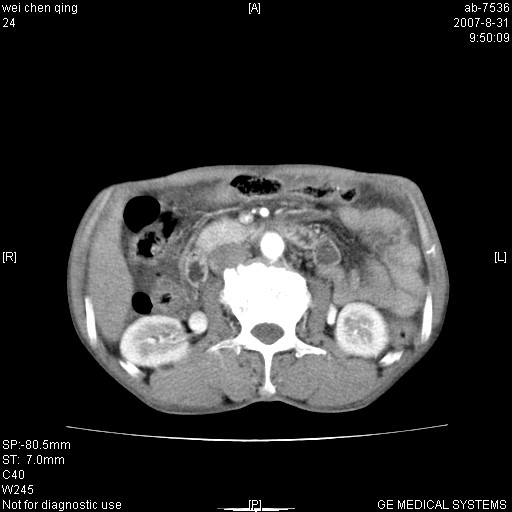

以下是引用zyyzzy在2007-8-31 14:34:00的发言:[br]该病人肝内胆管扩张,胆囊及胆总管未见明显扩张。在倒数第9层图像上可看到左右肝管结合部(肝总管)有软组织影,此处应薄层扫描。考虑肝总管占位(ca)、腹水。[br]